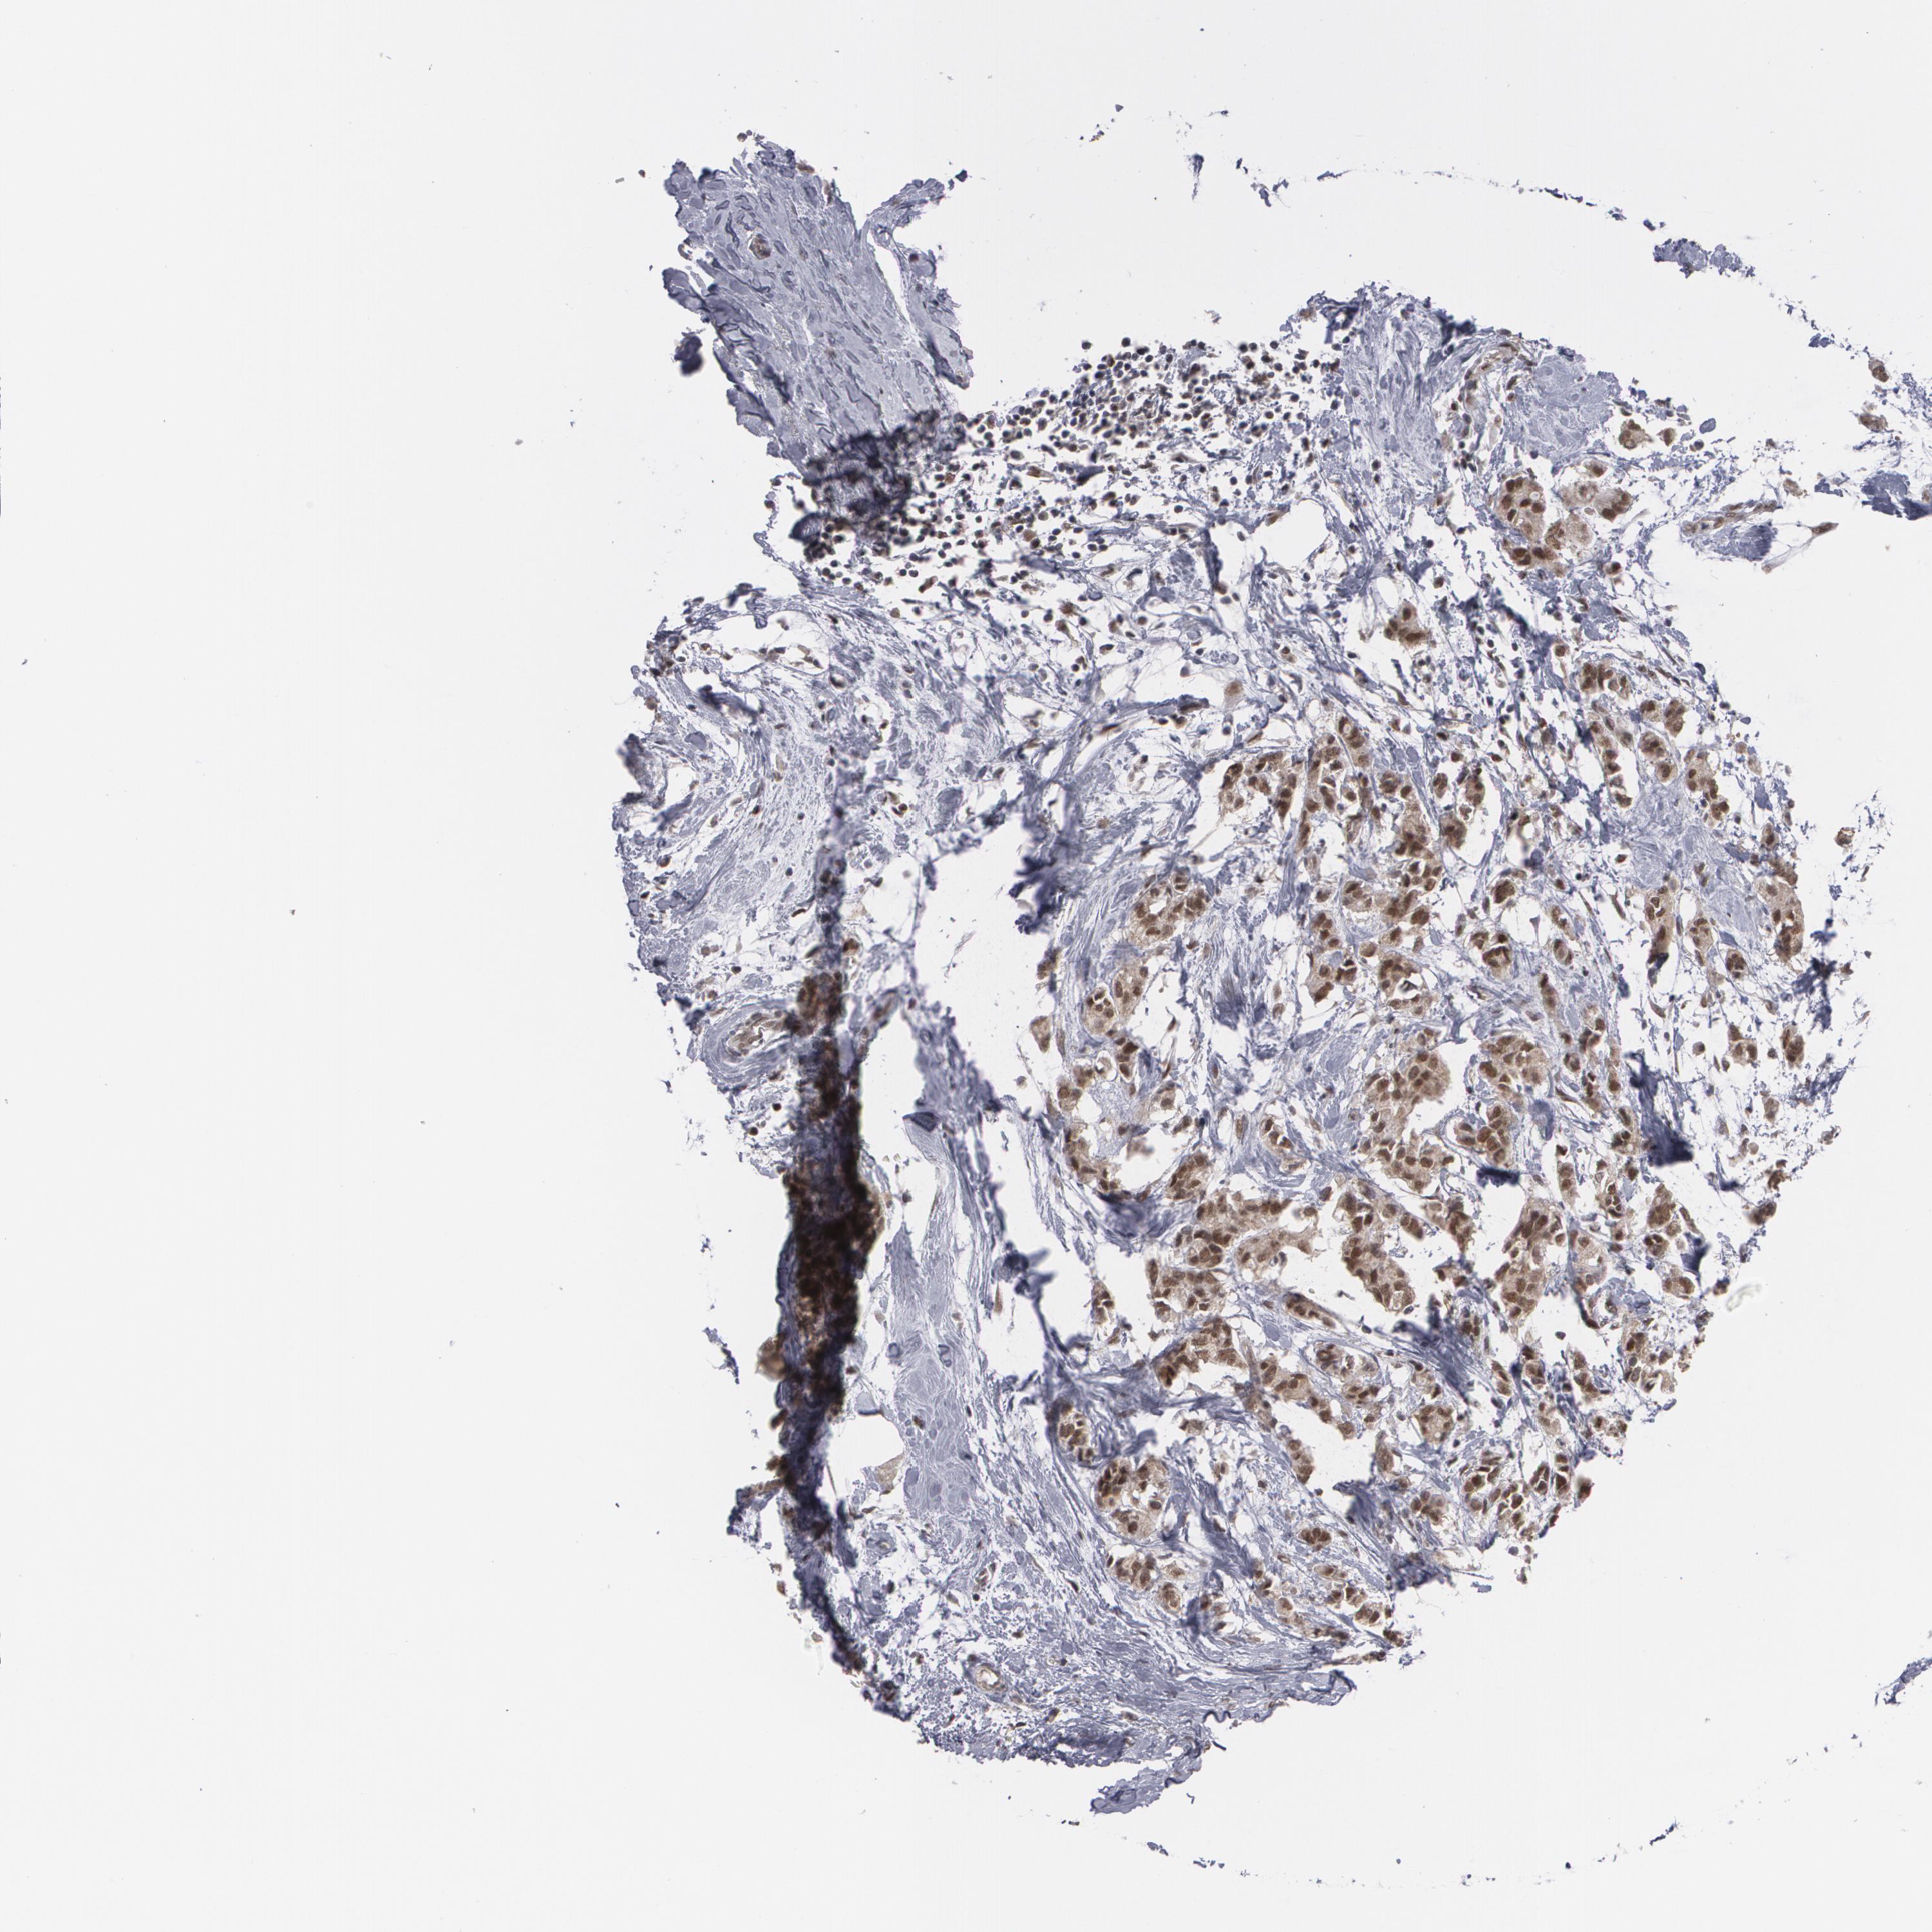

CANCER BREAST CANCER Show tissue menu

BRCA TCGA BRCA VALIDATION PROTEIN EXPRESSION